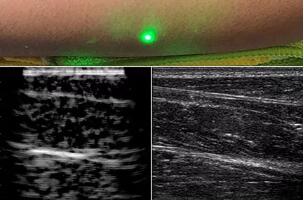

臨床應(yīng)用的無創(chuàng)超聲,要求探頭與人體皮膚直接接觸來向身體傳導(dǎo)高頻振動的超聲波。但是,有一些特定的患者卻在超聲檢查時受到限制,比如兒童、燒傷患者和敏感皮膚患者等。而近日麻省理工學(xué)院的研究人員證明,確實有可能使用激光在不接觸皮膚的前提下對患者進(jìn)行超聲波掃描。

而麻省理工學(xué)院的研究小組現(xiàn)在開發(fā)了一種使用激光檢測皮膚上超聲波振動的方法,以便可以使用一種激光使皮膚產(chǎn)生共振,而另一種則可以檢測到振動,從而達(dá)到“遠(yuǎn)程超聲掃描”的作用。

目前,研究人員已經(jīng)與健康的志愿者測試了他們的系統(tǒng):從半米遠(yuǎn)處掃描了他們的前臂,并將這些結(jié)果與傳統(tǒng)超聲的結(jié)果進(jìn)行了比較。他們能夠觀察到深達(dá)6厘米的組織,并能看到肌肉,脂肪和骨頭,并報告其結(jié)果可與標(biāo)準(zhǔn)超聲相媲美。

研究人員用一種激光裝置測試了這個想法,該裝置使用一個波長為1,550納米的脈沖激光來產(chǎn)生聲波,并使用第二個連續(xù)激光,調(diào)諧到相同的波長以遠(yuǎn)程檢測反射的聲波。第二個激光器是靈敏的運(yùn)動檢測器,可測量聲波從肌肉,脂肪和其他組織反射回來而引起的皮膚表面振動。反射的聲波產(chǎn)生的皮膚表面運(yùn)動會導(dǎo)致激光頻率發(fā)生變化,這種變化可以測量。通過機(jī)械掃描人體上的激光,科學(xué)家可以獲取不同位置的數(shù)據(jù)并生成該區(qū)域的圖像。